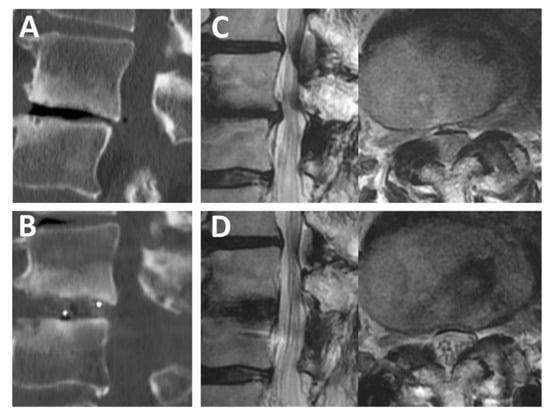

2.1. Patient Selection

2.2. Surgical Technique